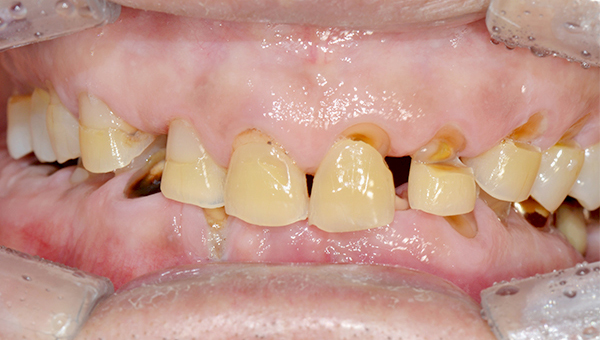

심*복 임플란트 시술 사례

전체 임플란트

2024.12.05

치료 전